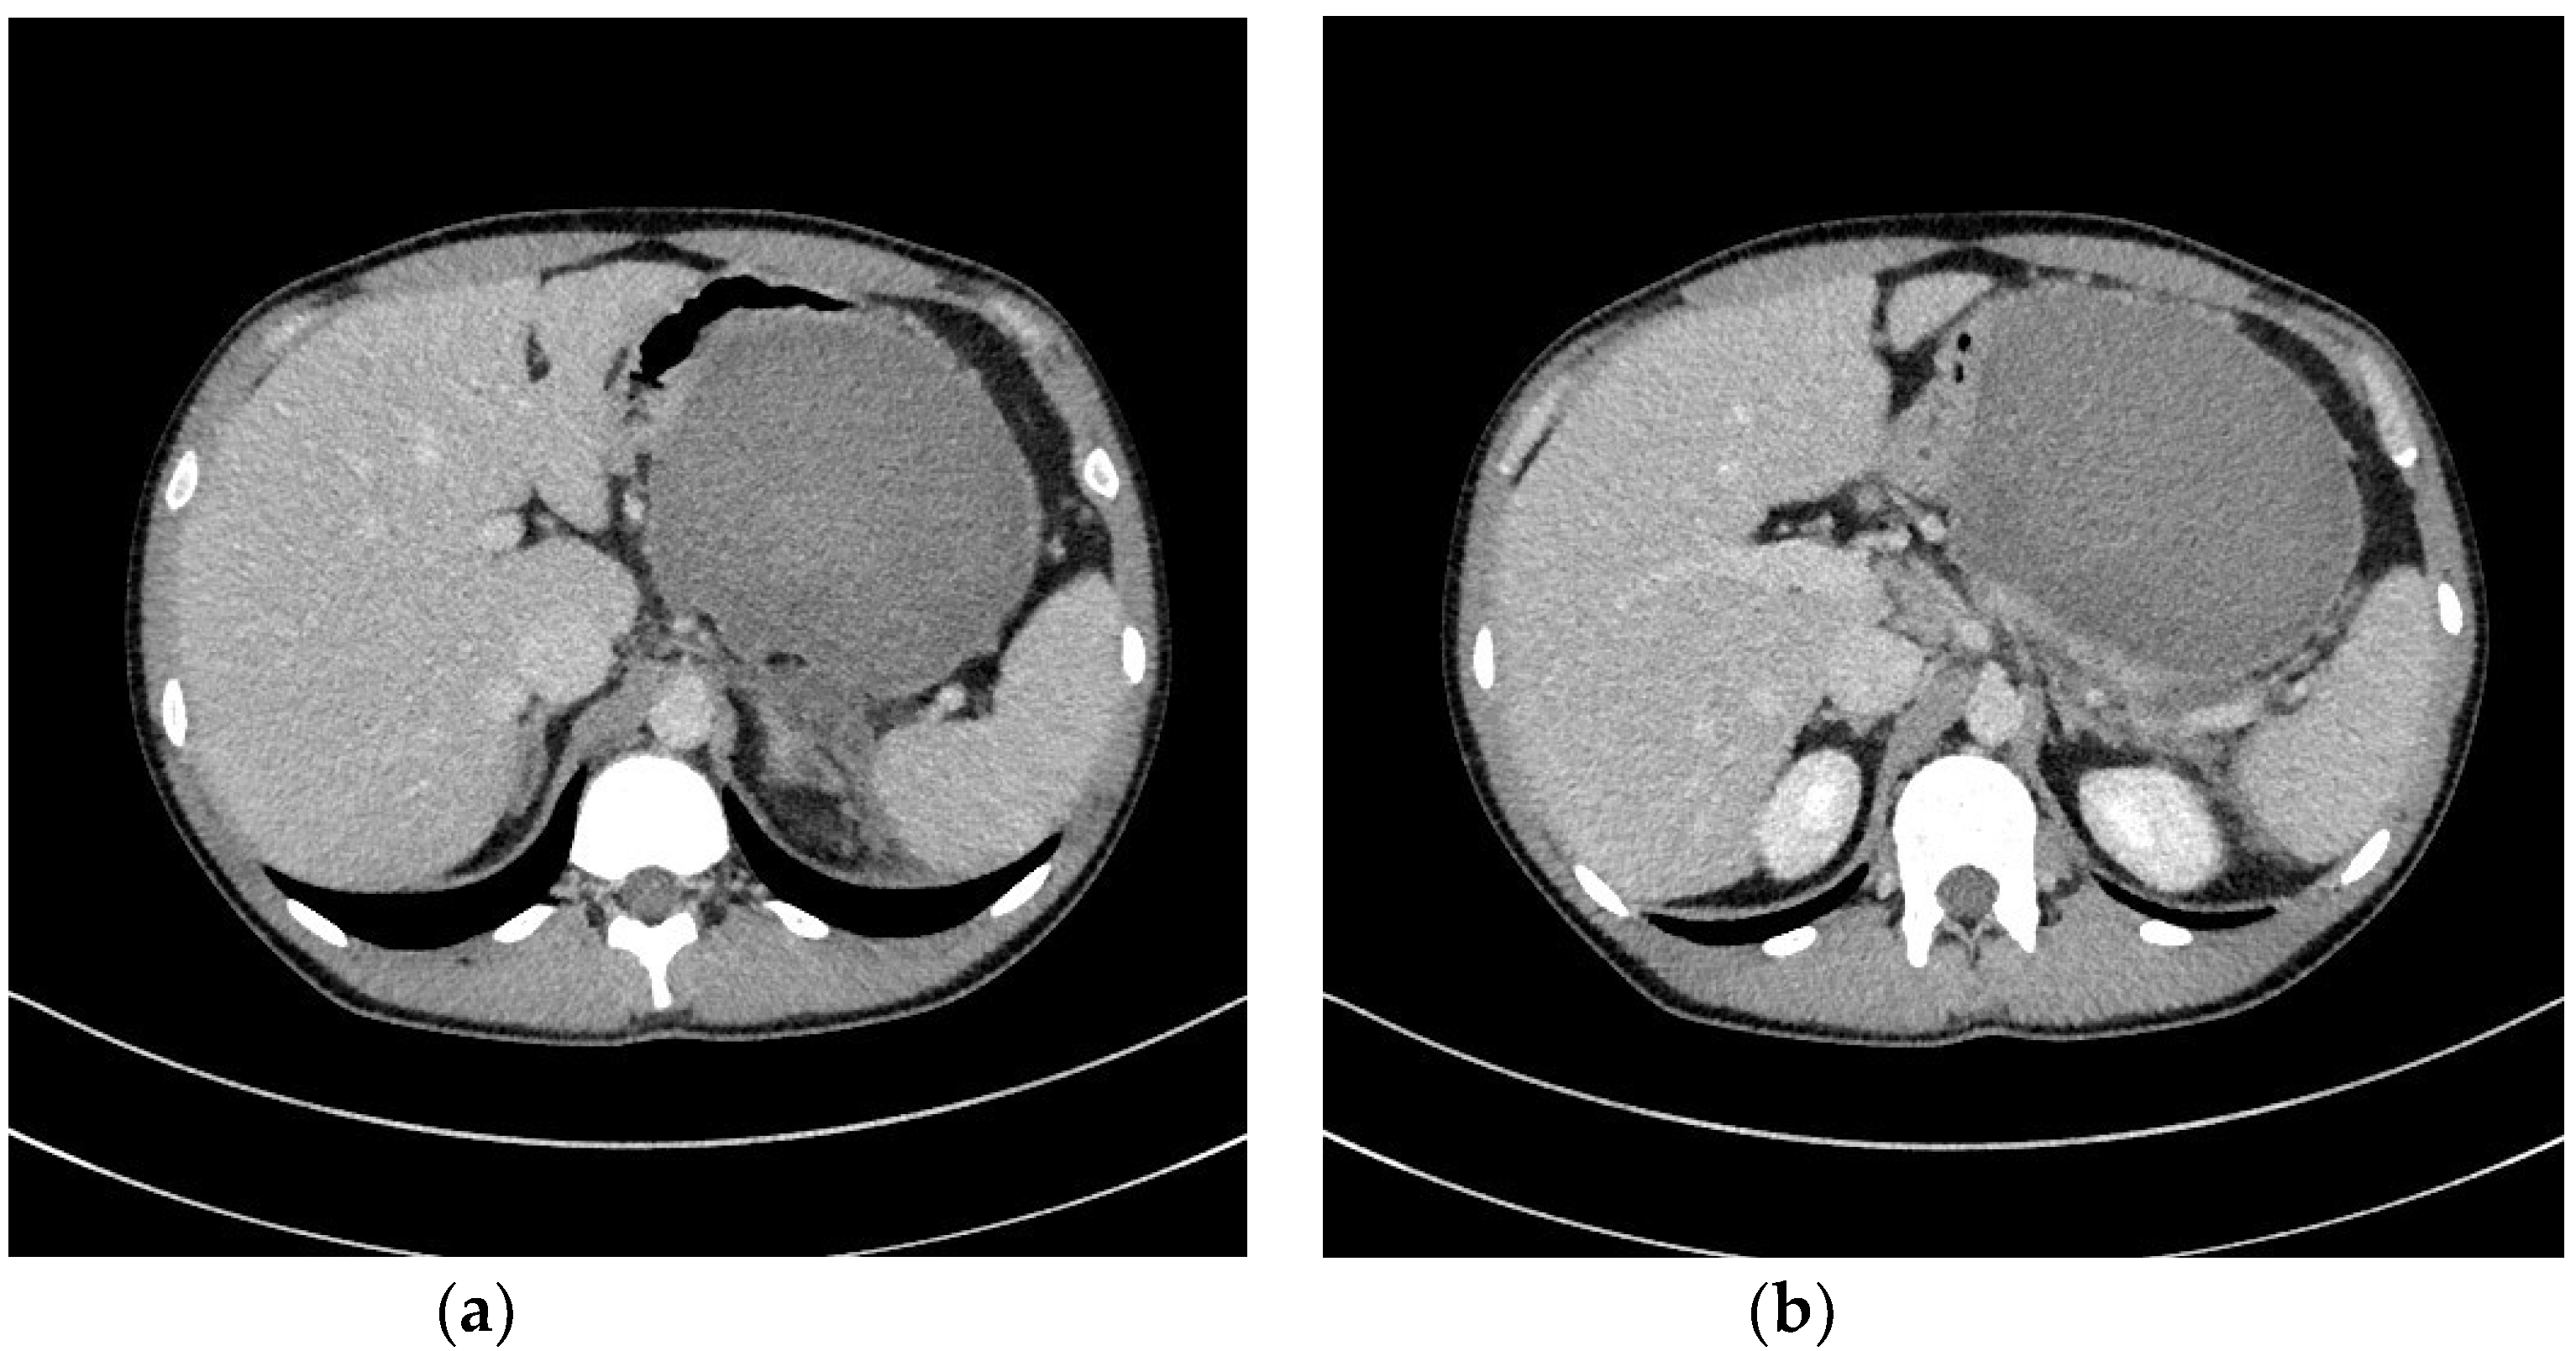

2. Strategy of Interventional Treatment

3. Transmural Endoscopic Drainage